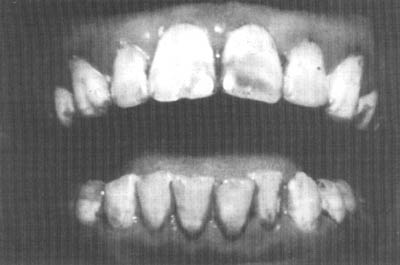

FOTO 37

Caries dentales

Carie dental es el término médico para las lesiones dentales o cavidades en los dientes. Empieza como una pérdida o destrucción de las capas del mineral externo de los dientes. Las caries tienden a ser progresivas, con pérdida de minerales y luego pérdida de proteína del diente y formación de caries (Foto 37). La caries puede ocasionar dolor, destrucción de los dientes y algunas veces la infección del tejido circundante (abscesos). La carie dental es un ejemplo de una interacción de la nutrición y la infección.